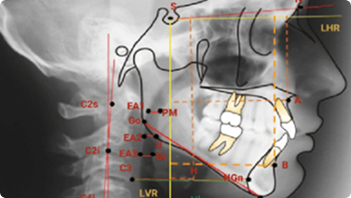

Cephalometric Tracing & Analysis